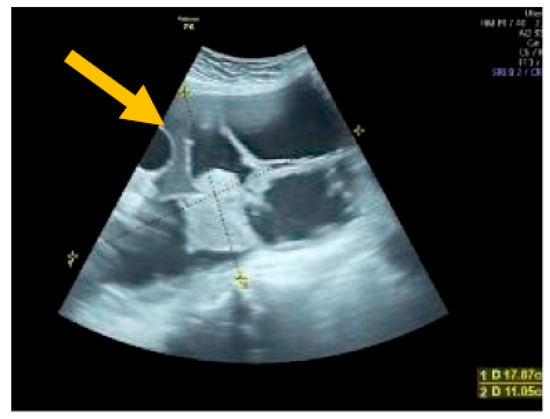

The existence of irregular solid tumors, ascites, at least four papillary structures, an irregular multilocular-solid tumor (diameter at least 10 cm), and very strong blood flow on a color Doppler assessment are malignant indicators, whereas a unilocular cyst, the presence of solid components (max diameter < 7 mm), the presence of an acoustic shadow, a smooth multilocular tumor (max diameter < 10 cm), and the absence of detectable blood flow on the Doppler predispose for the presence of a benign mass [24] (Figure 1, Figure 2 and Figure 3).

Figure 2. Multilocular solid tumor. (Yellow arrow indicates the presence of a cyst with multiple septums, measurable solid components, and papillary projections.)